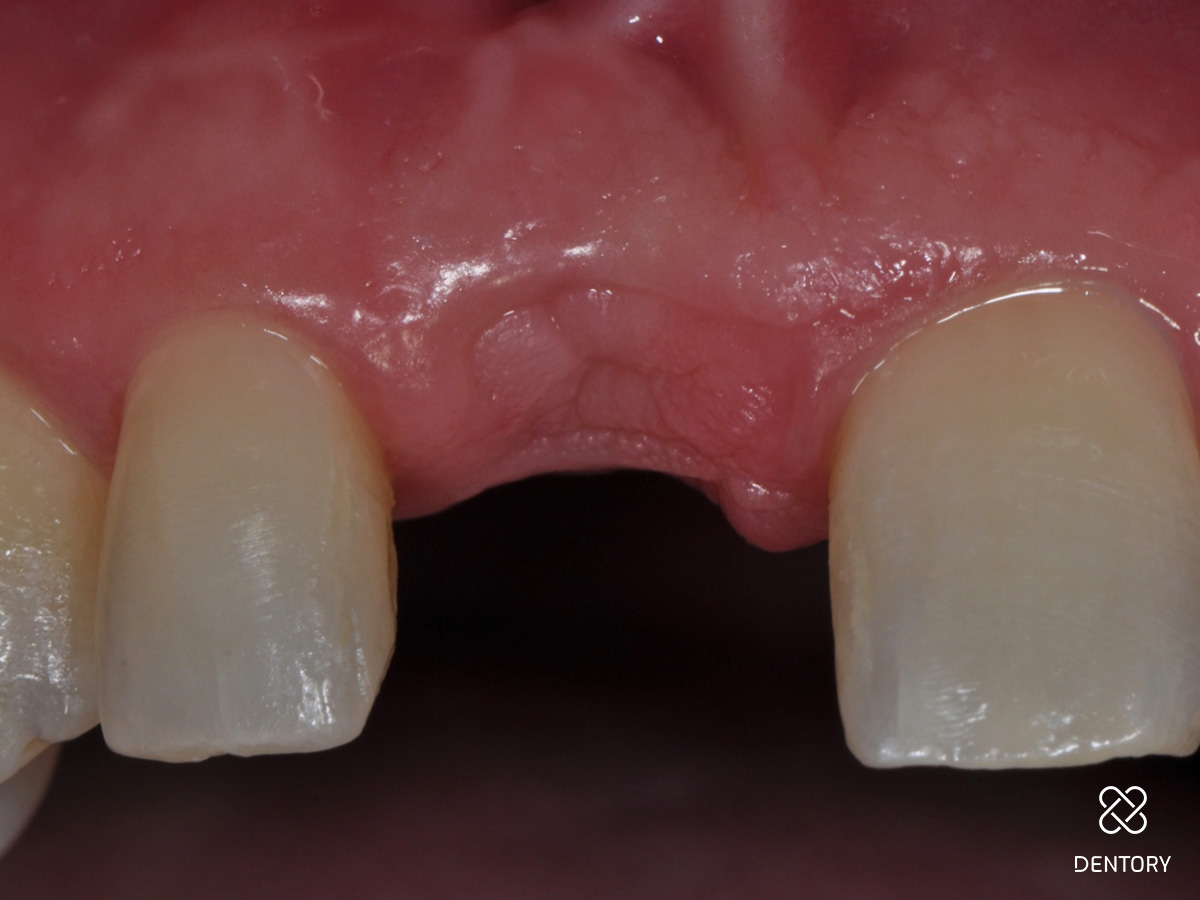

Abbildung 6

Nach der Extraktion sind die Längsfraktur der Wurzel und die deutlich apikale Positionierung des Wurzelstiftes erkennbar.